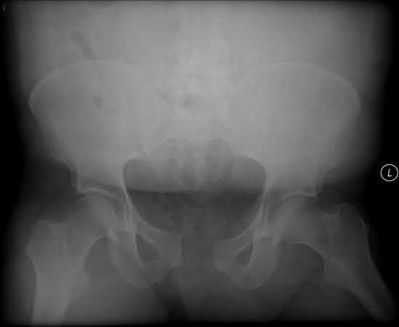

A 35 year-old female presents after prolonged extrication from a motor vehicle collision complaining of severe pelvic pain. Physical examination reveals diminished perianal sensation. She is otherwise neurologically intact. Figures A through D are radiographs and representative CT cuts of her injury. Which of the following nerve roots has likely been injured by the acute trauma?

The clinical scenario is consistent with a high-energy sacral fracture. The radiographs in figures A and B demonstrate a sacral fracture with posterior displacement of the right hemipelvis seen on the inlet view. Figures C and D are axial and sagittal CT images which show a displaced fracture of the right

hemisacrum along with a transvere fracture component through the S3 body . Diminished perianal sensation is concerning for an S2 nerve root injury.

Mehta et al reviewed the current management of sacral fractures. They note that the S1 and S2 nerve roots are more likely to be injured with sacral fractures as they occupy 1/3 to 1/4 of the neural foramina, as opposed to S3 and S4, which only occupy 1/6 of the neural foramina.

Robles reviewed the current literature to ascertain principles of evaluation and treatment for transverse sacral fractures. The author notes that injury to nerve roots S2 to S5 is manifested by impairment of urinary and anal continence and sexual function.

The first illustration demonstrates the sacral nerve root dermatomal distribution. The second shows a pelvic cadaver dissection demonstrating the sacral nerve roots as they exit the foramina.